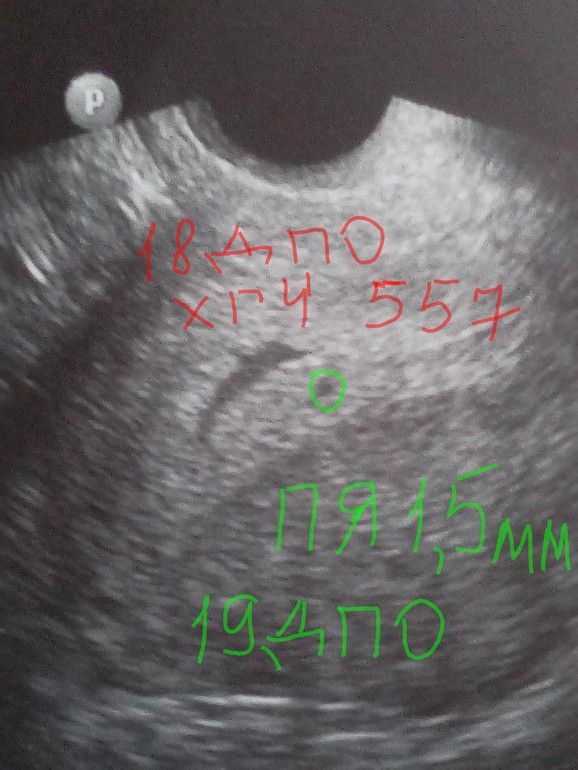

Изображение У меня в 4 недели и 3 дня был ХГЧ 557